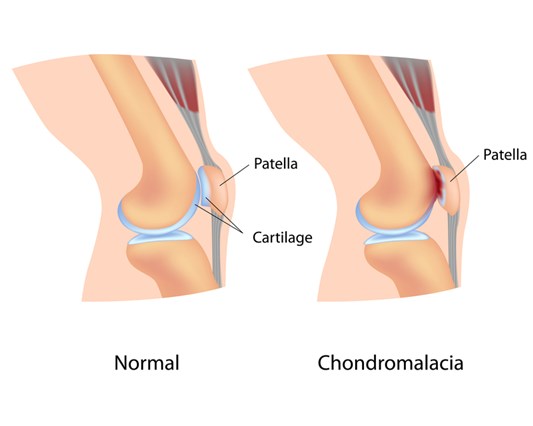

خشونة الركبة وتأكل المفاصل مشكلة يعاني منها نسبة كبير جدا من الناس حول العالم، بعض الأشخاص يمكنهم التعافي باستخدام بعض الأدوية والمسكنات، ولكن في الكثير من الحالات الخطرة تكون عمليات الركبة الصناعية هي الحل الوحيد لها حتى يمكنك العودة لممارسة حياتك الطبيعية مرة أخرى، وحتى تخضع للجراحة وأنت مطمئن يمكنك الاضطلاع على المقال التالي للتعرف بصورة أقرب عن هذه الجراحة.

كل جراحة تتدخل فيها بشيء بديل عن طبيعة جسدك بالتأكيد لا يكون بنفس الكفائة التي كان يتعامل بها العضو الأصلي ولكن في عملية تغيير المفصل قد يبعد الأمر قليلا فهو من الجراحات الخطرة، وتزيد المخاطر على المرضى الذين يخوضون عملية استبدال ركبة كاملة ويكون مفرط بالوزن، لذلك ينصح للمرضى الذين لديهم بدانة مفرطة أن يخسر من وزنه قبل العملية، أو أن يخضع لعملية جراحية لعلاج البدانة.

إن كسر أو قطع سطح البولي إثيلين المدخل على الظنبوب قد يكون مقلقاً، قد تصبح هذه الشظايا مستقرة في الركبة وتخلق الم بعد عملية تغيير مفصل الركبة أو قد تنتقل إلى أجزاء أخرى من الجسم بسبب التطورات الأخيرة في الإنتاج فقد تقلصت الأخطار إلى حد كبير ولكن على مدى العمر الافتراضي لاستبدال الركبة هناك احتمالية العودة لهذه المخاطرو وفيما يلي مضاعفات عملية تغير مفصل الركبة: